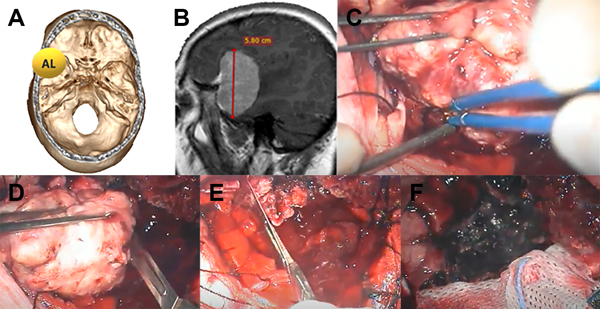

Luego del análisis estadístico propusimos una escala de graduación preoperatoria, con la cual según el puntaje total obtenido podemos inferir la probabilidad de exéresis total. Para la escala utilizamos la localización, el tamaño y la invasión ósea como parámetros (Figura 3, 4 Y 5).

Figura 4: Paciente con meningioma de base de cráneo anterolateral (AL) (1 punto), tamaño más de 5 cm (2 puntos) sin invasión ósea (1 punto), total: 4 puntos, moderada probabilidad de resección total. A: localización de lesión en base de cráneo. B: resonancia con contraste corte sagital prequirúrgica. C: imagen intraoperatoria en donde se observa meningioma con plano aracnoideo. D: vaciamiento y reducción de tamaño con bisturí hoja 11. E: resección parcial de duramadre y coagulación de la misma. F: lodge quirúrgica sin remanente tumoral, resección Simpson 2.